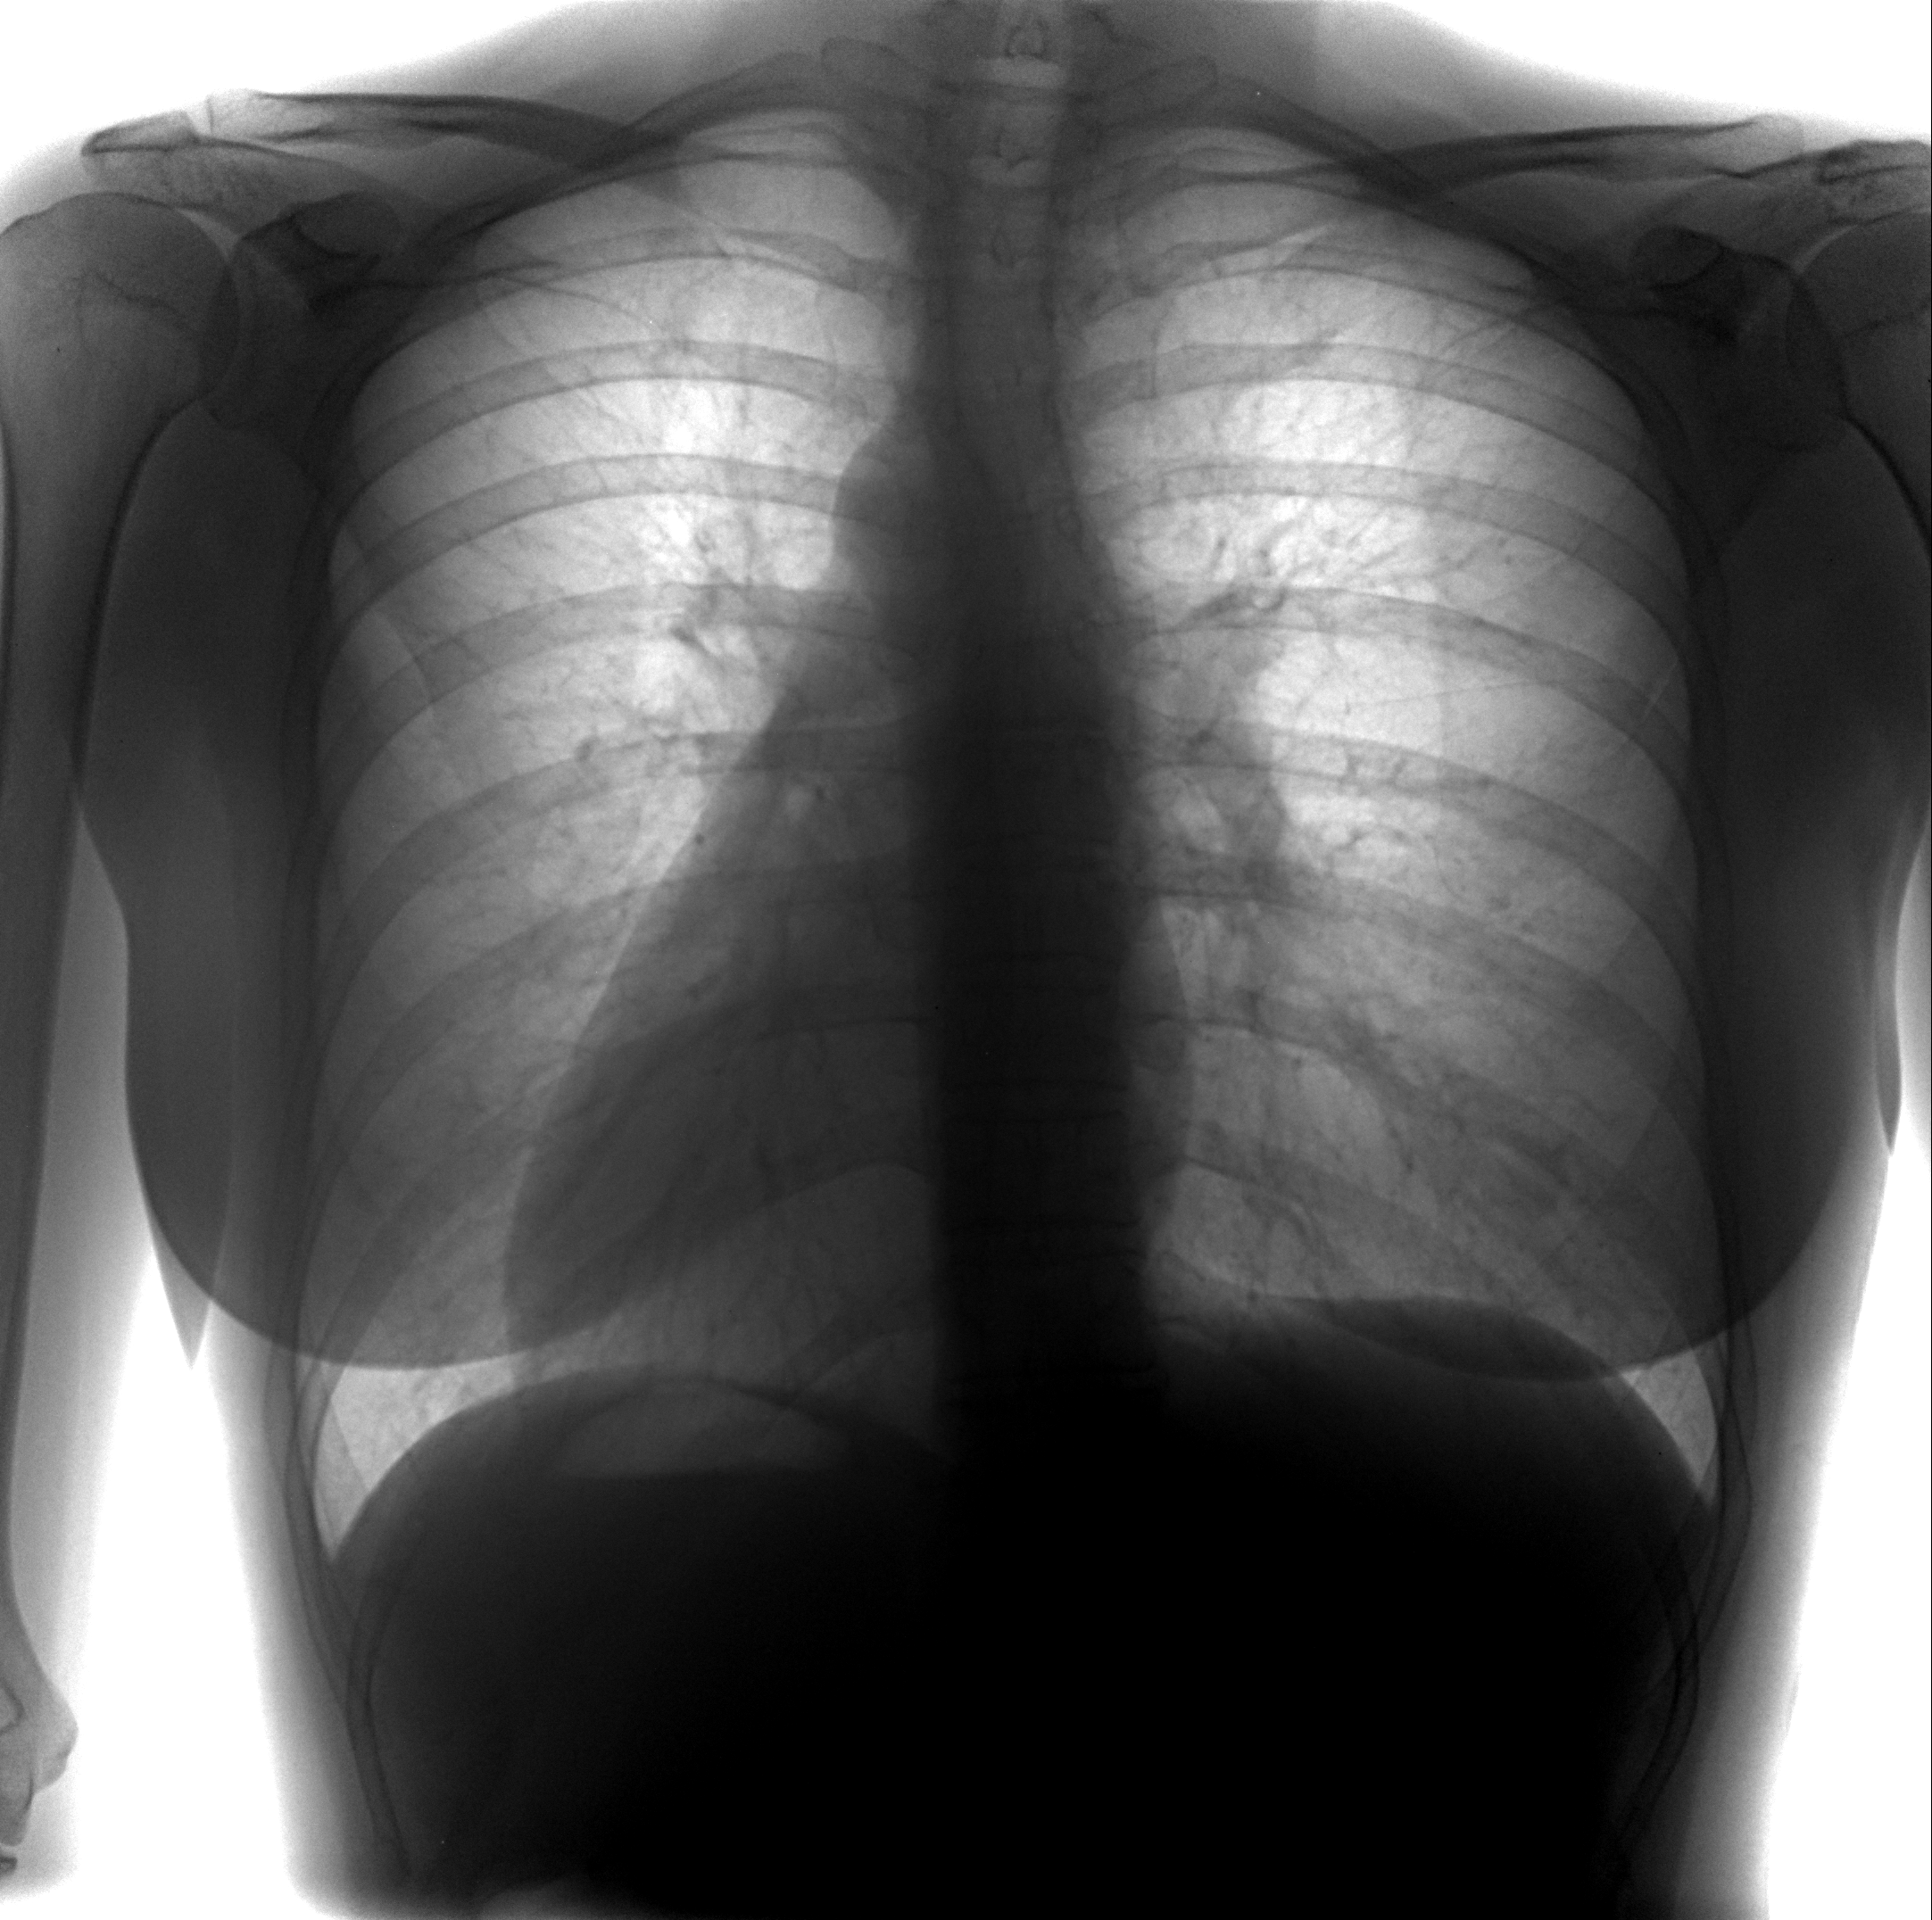

Рентген здоровых легких: примеры снимков и советы